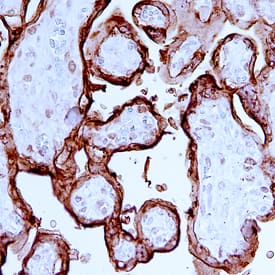

Placental Lactogen/CSH1 was detected in immersion fixed paraffin-embedded sections of human placenta using Human Placental Lactogen/CSH1 Monoclonal Antibody (Catalog # MAB5757) at 15 µg/mL overnight at 4 °C. Before incubation with the primary antibody, tissue was subjected to heat-induced epitope retrieval using Antigen Retrieval Reagent-Basic (Catalog # CTS013). Tissue was stained using the Anti-Mouse HRP-DAB Cell & Tissue Staining Kit (brown; Catalog # CTS002) and counterstained with hematoxylin (blue). Specific staining was localized to cytoplasm in syncytiotrophoblast cells. View our protocol for Chromogenic IHC Staining of Paraffin-embedded Tissue Sections.Applications for Human Placental Lactogen/CSH1 Antibody

Immunohistochemistry

Sample: Immersion fixed paraffin-embedded sections of human placenta